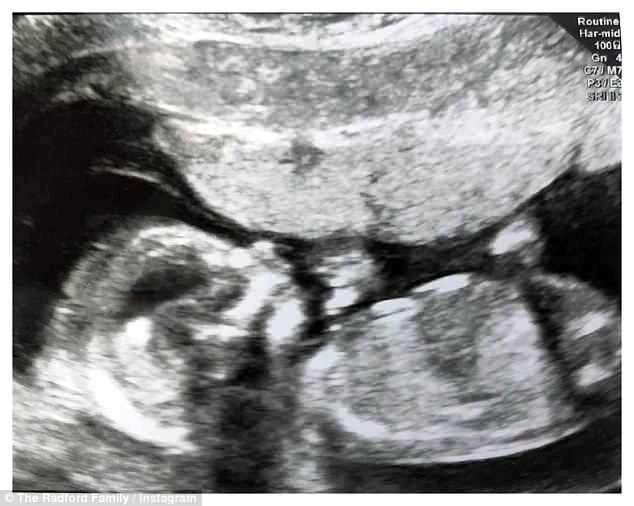

Bà mẹ 43 tuổi này vừa sinh con vào tháng 9 năm ngoái và hứa rằng đây sẽ là đứa trẻ cuối cùng. Tuy nhiên, giờ bà cho biết đã lại mang thai và đồng thời đăng bức ảnh siêu âm đứa bé trong bụng lên trang cá nhân Instagram.

Hai vợ chồng bà Radford khoe ảnh siêu âm em bé sắp ra đời. Ảnh: YouTube

"Cha mẹ không thể đợi để chào đón con đến với gia đình của chúng ta" - bà Radford đăng kèm theo bức ảnh trên Instagram.

Ảnh siêu âm em bé mới. Ảnh: Instagram